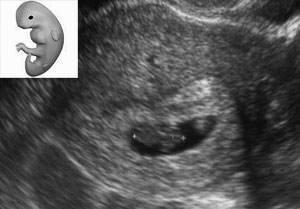

Nagyon halkan jegyzem meg, hogy úgy néz ki: IGEN.![]()

Igaz, csak holnap lenne a ciklus utolsó napja, ha a peteérést nézem, de napok óta egyre erősebb a tesztem.

Apával úgy döntöttünk, hogy ez a baba már csak 8 hónap múlva bújik ki belőlem makkegészségesen.